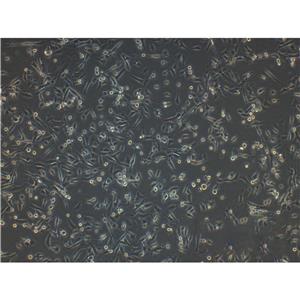

"MNNG/HOS Cells人骨肉瘤细胞系(提供STR图谱)

" "传代比例:1:2-1:4(首次传代建议1:2)

" "背景信息:骨肉瘤;女性

" "换液周期:每周2-3次

" "生长特性:贴壁

" "MNNG/HOS Cells人骨肉瘤细胞系(提供STR图谱)

" "形态特性:详见细胞说明书

" "MNNG/HOS Cells人骨肉瘤细胞系(提供STR图谱)

" "MNNG/HOS Cells人骨肉瘤细胞系